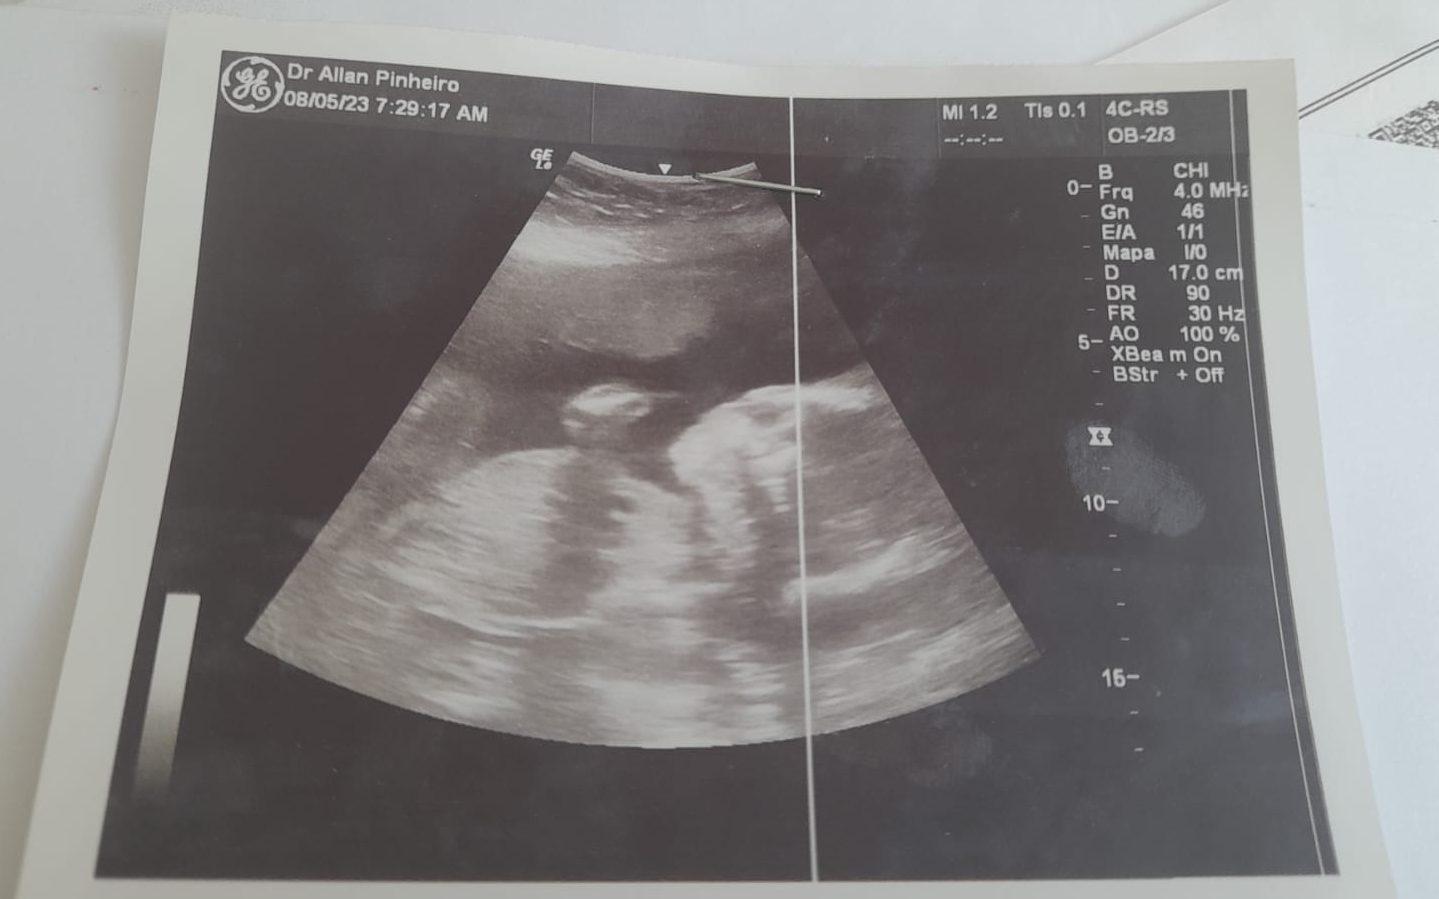

No último domingo, a jovem realizou uma ultrassonografia que confirmou que o neném estava morto. A mãe explica que ela teve pressão alta, o que causou a morte.